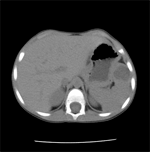

We asked for a Chest CT scan